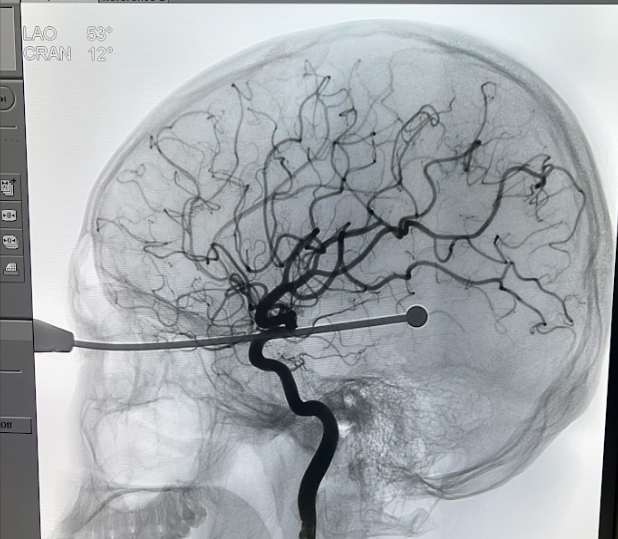

Người bệnh được chuyển từ khu vực hồi sức cấp cứu xuống phòng can thiệp mạch máu, gây mê nội khí quản, đặt ống thông từ động mạch đùi lên phía các động mạch não, kiểm soát các mạch máu nằm trên đường đi của dị vật.

Ca mổ kéo dài gần 1 giờ đồng hồ tính từ lúc bệnh nhân bắt đầu được gây mê. Các bác sĩ đã rút bỏ dị vật ra khỏi mắt nam thanh niên mà không ghi nhận có tổn thương mạch máu nào. Đặc biệt, phim chụp kiểm tra được thực hiện ngay tại bàn can thiệp.